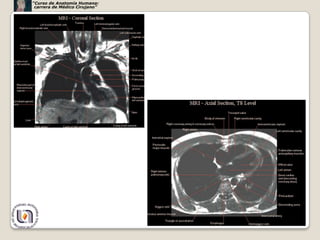

Ao

P

vcs

ai

ad

vi

vci